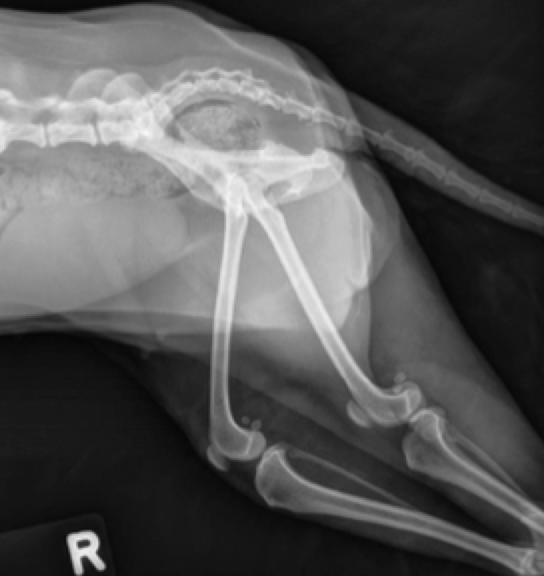

Ununited Anconeal process

happens when the growth plate is not fused, especially if the ulna is growing slower than radius

earliest it is united → 5 months

tx

NSAIDS

can take the piece out or insert metal plates